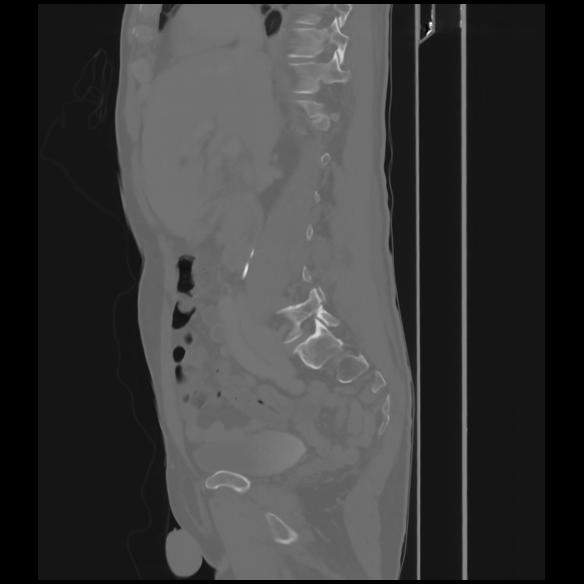

7 CUERPO,CE,Sagittal,3.000,CUERPO,Sagittal,